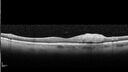

Severe diabetic tractional retinal detachment one year following diagnosis of type II Diabetes Mellitus245 views44 year old man The vision in the left eye started to decline about 4 days ago. Prior to that the left eye was the better eye. He was diagnosed with diabetes a year ago.Â

VA OD: Dcc20/50-1 OS: Dcc20/125-2, TP: OD:12 OS:13

Following two surgeries in each eye, silicone oil remaining forever, monthly anti-VEGF for severe DME - BCVA OU 20/200 at 3 yearsAug 17, 2022